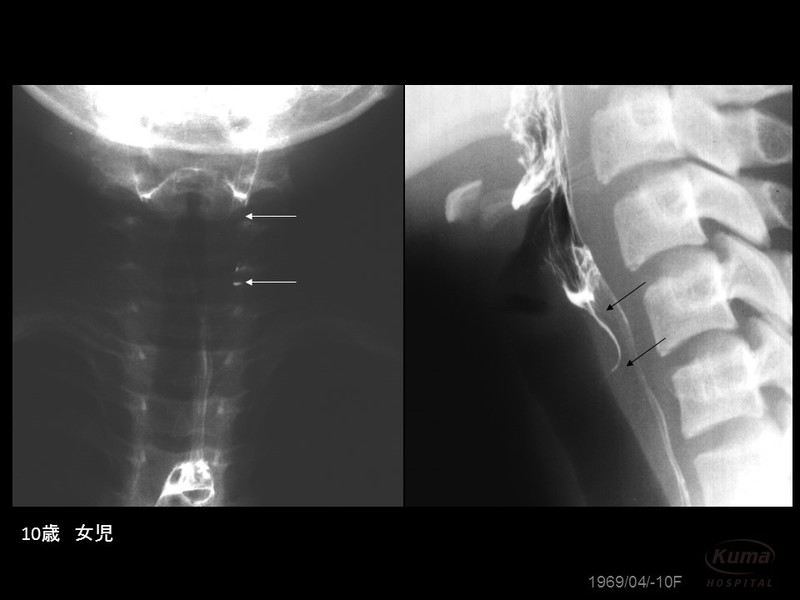

このほかに、左前頸部に排膿が起こっている10歳の女児も受診されています。梨状窩には、写真のように細い瘻孔が認められました。

(左前頸部に炎症があり、すでに排膿がみられる。 症例写真提供:宮内昭先生)

(梨状窩から伸びる細い瘻孔 写真提供:宮内昭先生)